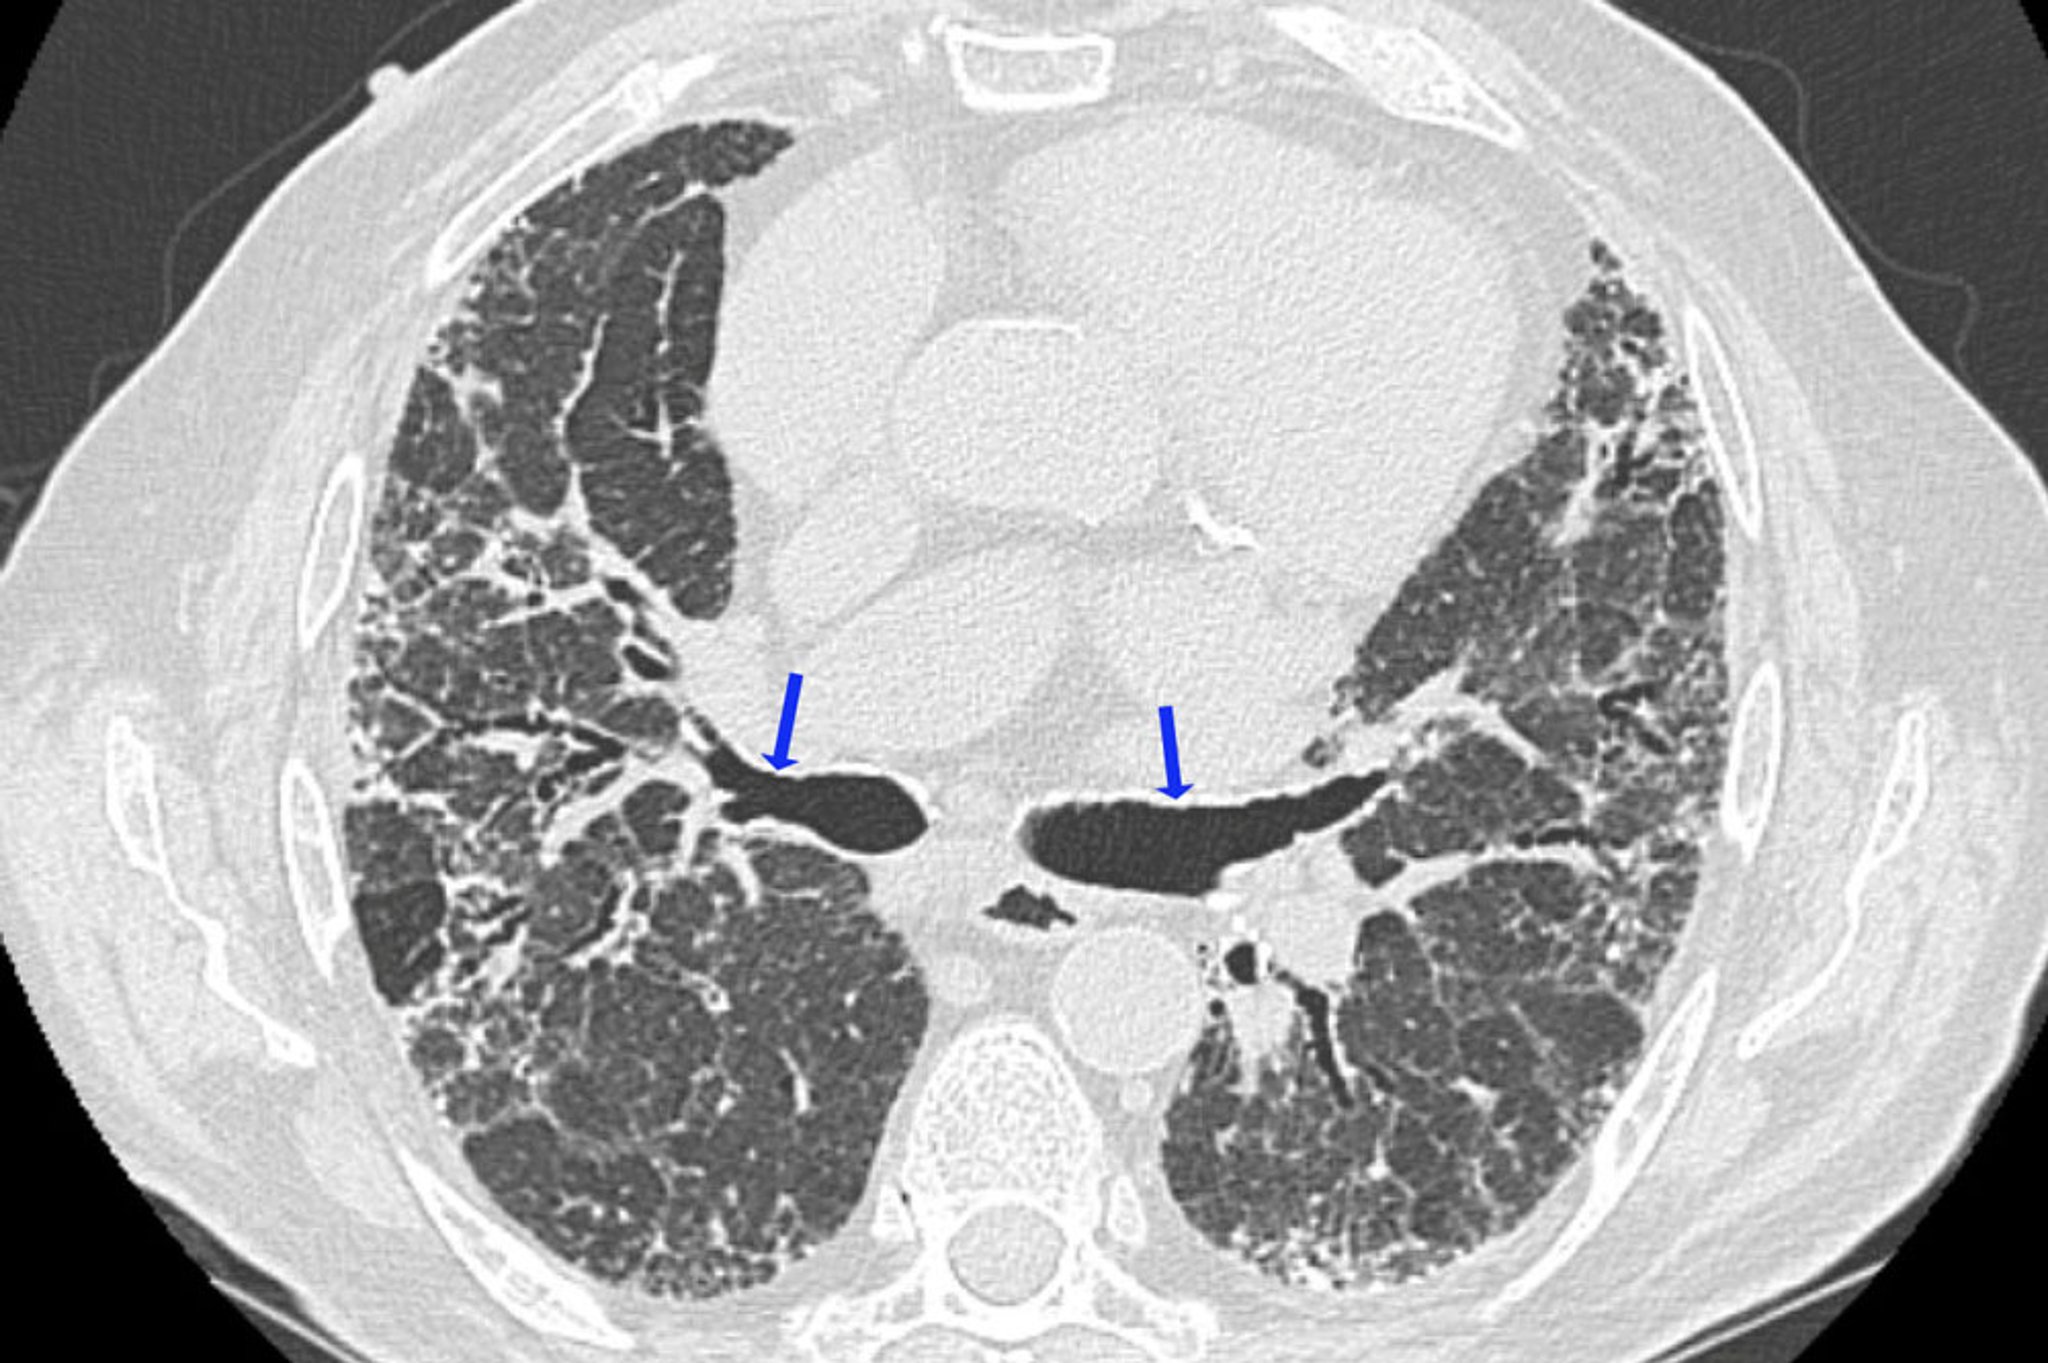

La TC de alta resolución es la modalidad de diagnóstico por imágenes de elección para evaluar cambios parenquimatosos en la neumonitis por hipersensibilidad, y es más probable que muestre anormalidades que la TC convencional o las radiografías (2).

En las neumonitis por hipersensibilidad aguda y subaguda, los hallazgos más típicos en la TC de alta resolución son micronódulos centrolobulillares, que miden en forma típica menos de 3 mm de diámetro, usualmente ubicados cerca de las vías aéreas centrales de esos lobulillos. En ocasiones, la opacificación (atenuación) en vidrio esmerilado es el hallazgo predominante o a veces el único. Es generalmente difuso, pero a veces perdona la periferia del lóbulo secundario. Áreas focales de hiperclaridad, similares a los presentes en la bronquiolitis obliterante, pueden ser una característica destacada en algunos pacientes (p. ej., atenuación en mosaico con atrapamiento de aire en la TC de alta resolución espiratoria).

En la neumonitis por hipersensibilidad crónica, hay hallazgos de fibrosis pulmonar, que incluyen pérdida de volumen lobular, opacidades lineales o reticulares, aspecto en panal de abejas y bronquiectasias por tracción. Pueden aparecer micronódulos centrolobulillares, opacificación en vidrio esmerilado y áreas de hiperlucencia, pero son menos prominentes. Algunos pacientes no fumadores con neumonitis por hipersensibilidad crónica tienen hallazgos de enfisema del lóbulo superior. La linfadenopatía mediastínica es infrecuente, lo que permite distinguir la neumonitis por hipersensibilidad de la sarcoidosis.